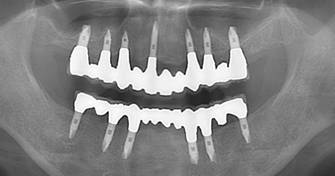

術前パノラマレントゲン写真。根の周りが黒くなり、骨がなくなっていることがわかります

治療後。歯周病で失われた骨が回復しています。使用インプラントはスプラインツイストです。

インプラント装着後6年。順調に経過しています。12か月毎のメインテナンスをしています。